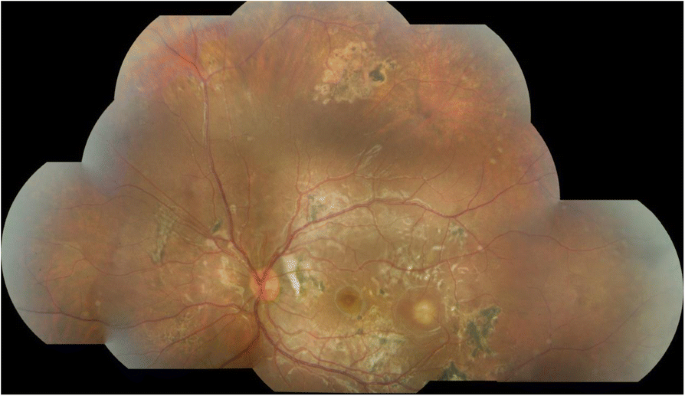

Following diagnosis of DUSN, diode laser was performed under general anaesthetic to the superior area of active chorioretinitis and presumed nematode. The patient was also commenced on oral albendazole 200 mg twice daily for 1 month and a reducing course of oral prednisolone starting at 25 mg daily and tapered over 30 days. After another month, her visual acuity had improved further to 6/9 and the treated area of chorioretinitis superior to the optic disc had disappeared. However, new areas of chorioretinitis had appeared temporal to the superotemporal arcade and in the inferonasal fundus (Fig. 5). A further course of oral albendazole 200 mg twice daily and oral prednisolone 7.5 mg was commenced and planned for 30 days but was discontinued by the patient after 2 weeks. After a further 2 months, the fundal appearance had changed once again and new areas of chorioretinitis had appeared in the superotemporal retina with resolution of the areas inferonasally and temporal to the superotemporal arcade (Fig. 6). Further laser was administered to the new superior lesion where a nematode was suspected. Despite additional anti-helminthic treatment with ivermectin, recurrence of active chorioretinitis lesions continued and electrophysiology testing indicated significant left retinal dysfunction.

A specialist uveitis opinion was sought from a tertiary centre in London that concurred with the diagnosis of DUSN; but it was thought that a secondary immune-mediated inflammatory response might be contributing to the clinical picture. Another tapering course of oral prednisolone along with mycophenolate mofetil was trialled without success. At last review, 19 months from initial presentation, the fundal appearance continued to change and a new area of focal chorioretinitis had appeared at the temporal macula (Fig. 7).